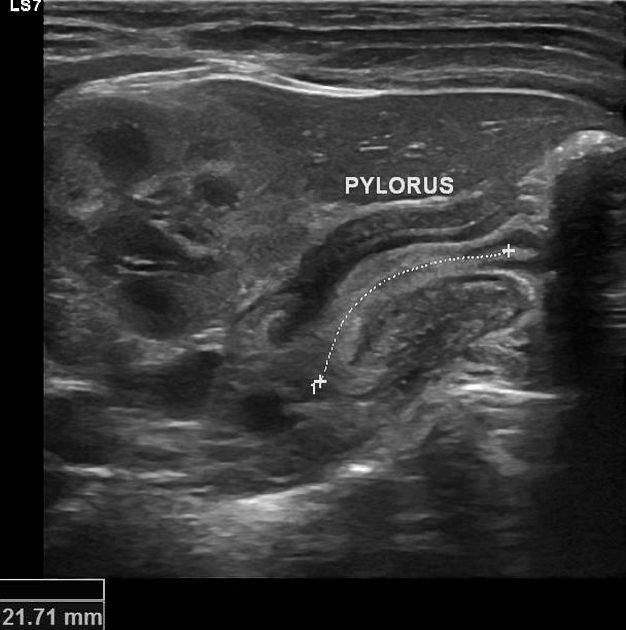

This is a classic presentation of pyloric stenosis. As the child is vomiting profusely, there will be an electrolyte imbalance. Hypokalaemia may be present and therefore needs to be corrected immediately. In reality, one would take blood for serum potassium levels and arrange an abdominal ultrasound while waiting for the serum potassium results. However, the exam writers want you to think about which is the most important given the stem.

Pay attention to the final line of the question.

If the question is asking for the NEXT STEP of action, serum potassium levels would be appropriate.

If the question is asking for the NEXT STEP TO DIAGNOSE the condition, then an abdominal ultrasound would be the answer. Intravenous fluid should follow after taking blood.

Presentation:

- Projectile non-bilious vomiting

- Age group: 3-8 weeks

- Olive-sized abdominal mass

- The child will feel hungry and want to feed despite constant vomiting

Diagnosis:

- Abdominal ultrasound

Treatment:

- Metabolic alkalosis : correct electrolyte imbalance + hydration

- Then referral to paediatric surgery (pyloromyotomy) + nasogastric tube.